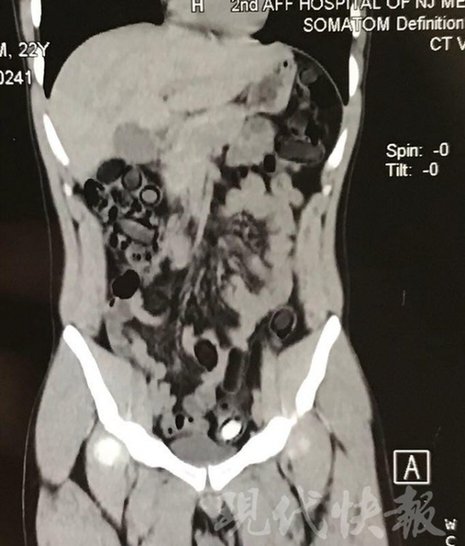

由于毒品在體內(nèi)一旦泄露有可能致命,警方第一時間將阿永帶到醫(yī)院進(jìn)行檢查。CT 掃描的結(jié)果顯示,阿永體內(nèi)布滿了密密麻麻的白色圓柱狀固體,就像一粒粒的蠶蛹。在南京市公安局鼓樓分局二板橋派出所,阿永分四次排出了毒品,毛重369.99克。經(jīng)訊問,阿永交代了自己全部的犯罪事實(shí)。目前,阿永已被刑事拘留。